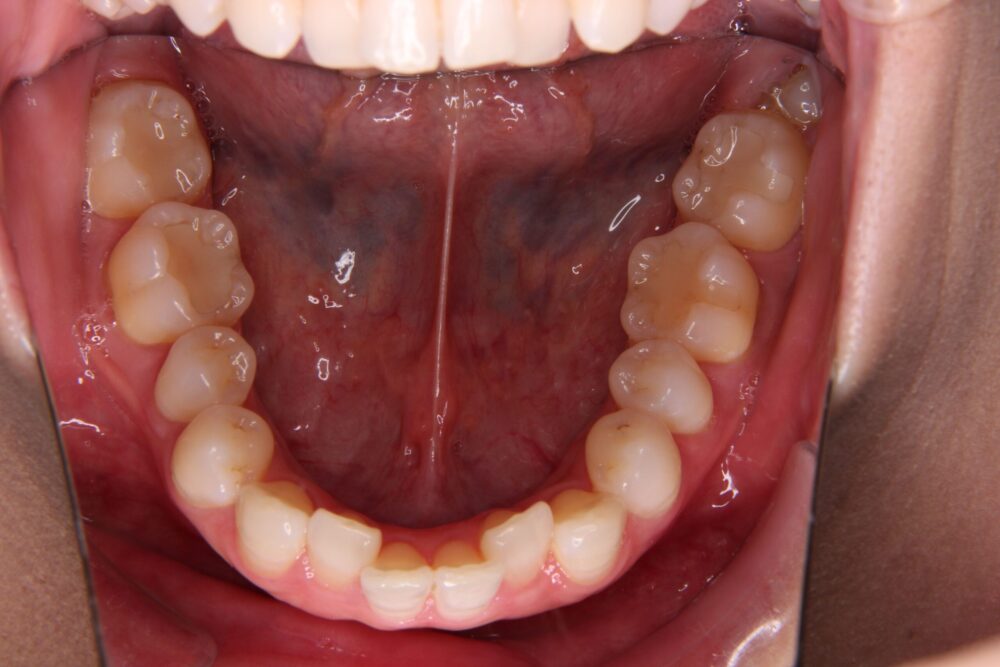

私自身は、特に、「前突」と「下顎の叢生」「過蓋咬合」が気になっていました。

矯正治療前の歯列がこちらです↓↓↓